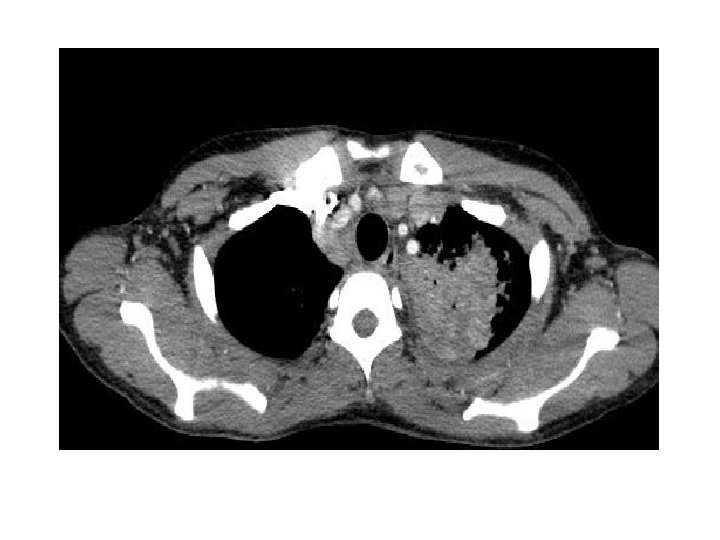

• Traitement de la tuberculose pulmonaire – Quadrithérapie débutée le 07 mai 2011 • Traitement de l’infection par le VIH – Truvada® Sustiva® le 19 mai 2011 (J 12) • Le 24 mai 2011 – Persistance de la fièvre (T=39 -41°C) – Scanner thoraco-abdomino-pelvien • Syndrome de masse ganglionnaire hilaire bilatéral sous carénaire, loge de Barety, latéro-trachéal et médiastinal • Foyer de condensation pulmonaire gauche • Transfert au CHU le 27 mai 2011